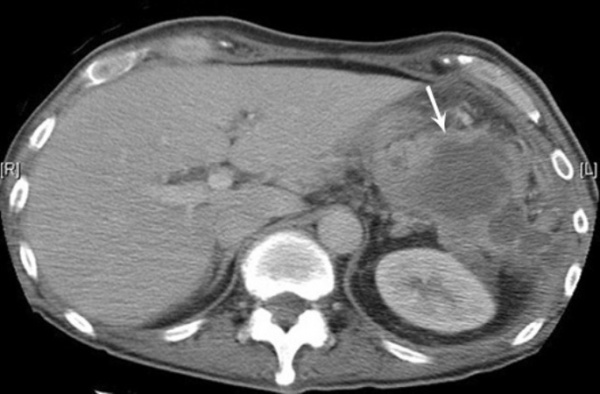

Абсцесс печени чаще всего возникает в результате распространения инфекции по сосудистому руслу из воспалительных очагов других органов или тканей брюшной полости (аппендицит, холангит, язвенный колит). Абсцессы могут быть одиночными или множественными. Для заболевания характерна высокая температура, озноб, боль и тяжесть в области печени, увеличение ее размеров.

Абсцесс в печени

Абсцессы брюшной полости встречаются в 30-35% у больных гнойным перитонитом. Обычно они располагаются в отлогих областях живота: подпеченочном, поддиафрагмальном пространстве, в подвздошных ямках и т.п. Клинике формирования абсцесса соответствует ухудшение состояния после небольшого светлого промежутка на фоне воспалительного заболевания брюшной полости (аппендицита, холецистита), наблюдается усиление интоксикации и боль в животе.

- Другие визуализационные методики. УЗИ брюшной полости наиболее информативно при абсцессе верхних ее отделов. При сложностях дифференциальной диагностики показано проведение КТ, диагностической лапароскопии.